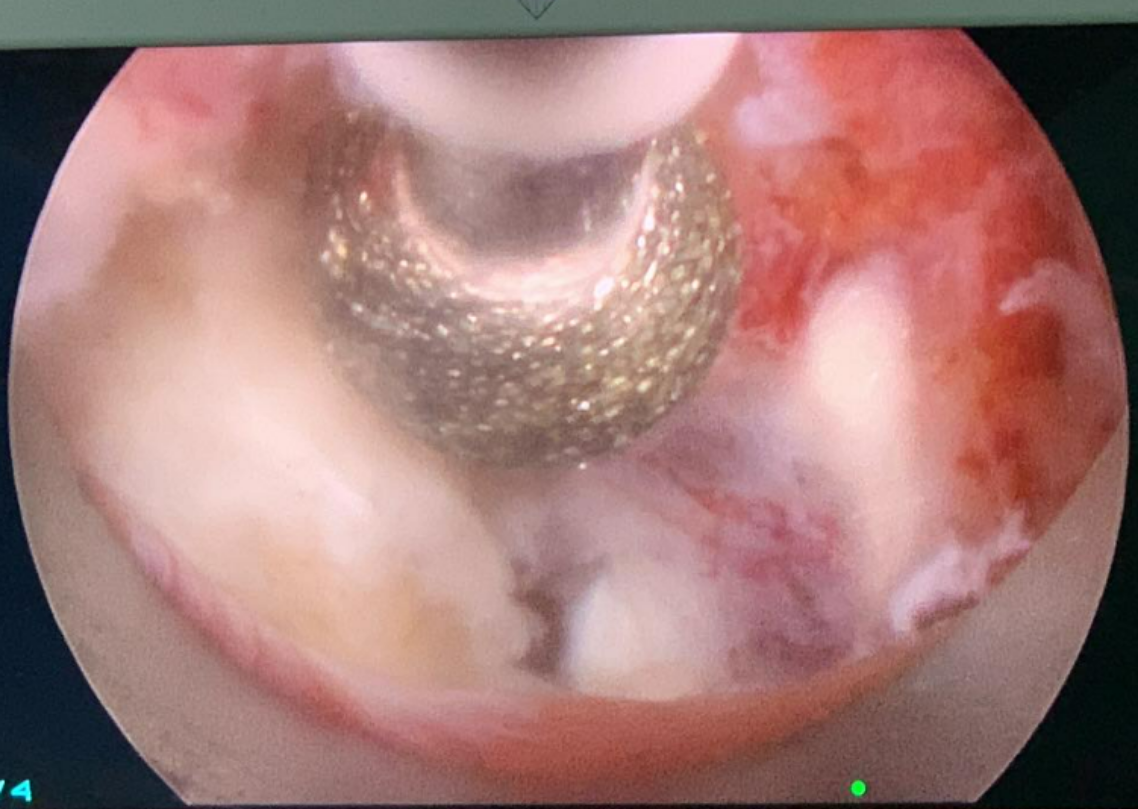

內視鏡手術則是在下背開1公分左右傷口,使用內視鏡在椎體之間作業,切除突出的椎間盤讓被壓迫的神經獲得減壓。